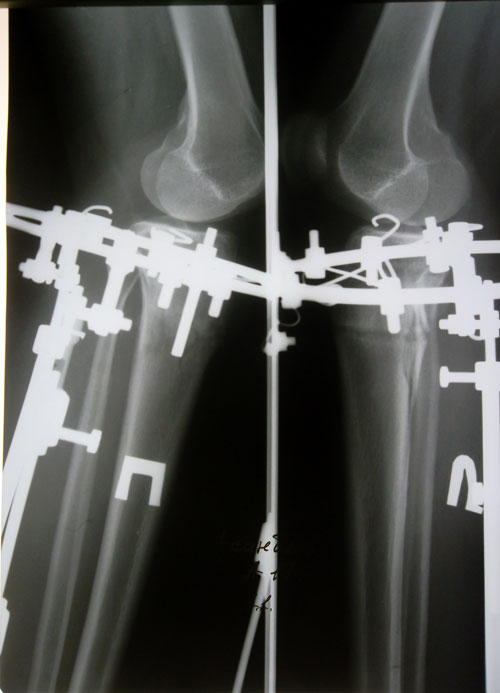

- Диагноз: О-образная деформация ног

Очень рада за вас, что всё хорошо! Ножки классные получаються! И снятие не за горами, было бы хорошо до ногово года)) хотья идея оформить аппараты мишурами и встречать новый год как вы говорите, тоже не плохо)) Удачи вам дорогая и всего хорошего!